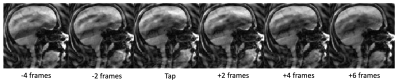

Figure 3: Dynamic Strip of images around a tongue tap. Showing from 4 frames before at a rest position, to the tongue tap, and then to 6 frames post tap showing a return to the resting tongue position.

Figure 3 shows a strip of images (skipping every other frame for better visualization of motion) right before, during, and after a tongue tap. The 10 frames comprise 766 ms of total time. In this figure, you can clearly observe the tongue elevate to the alveolar ridge (front part of roof of the mouth) and return to its resting position. In order to create a time series of activity for fMRI analysis, a pixel was placed near the point of contact for the tapping and the mean signal was filtered and detrended to make an indication of the tongue tapping, shown in Figure 4. Figure 4 also shows the time plot for a strip of pixels through the tongue tip, showing the tongue push forward and upward as it elevates. Using the timings from the taps identified from the dynamic time series, a functional MRI analysis was conducted using FEAT7 in FSL on the functional MRI images. Activation in the sensorimotor tongue region is shown in Figure 5, along with some spurious motion-related activations.